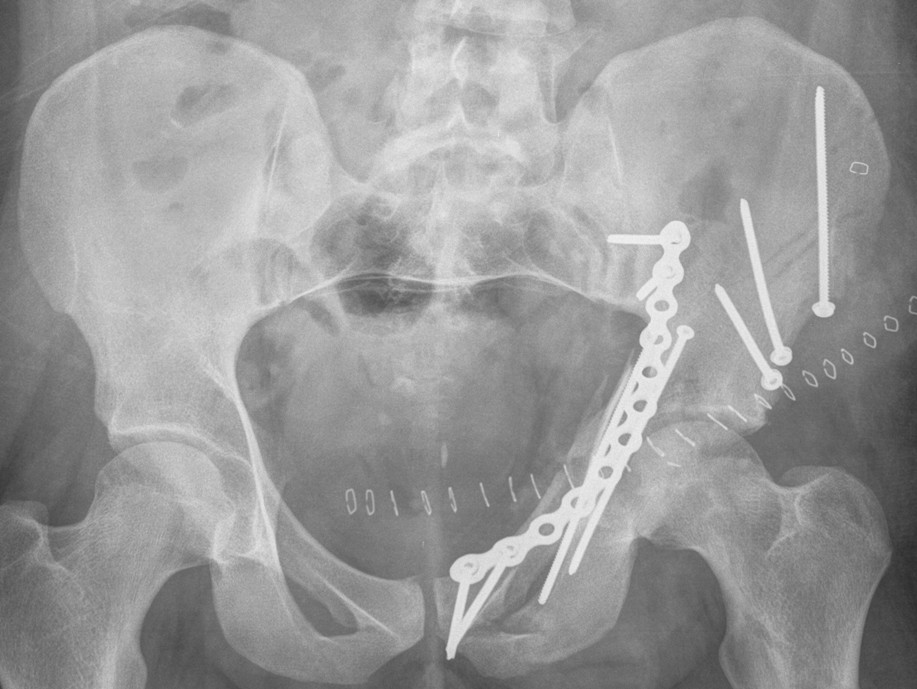

Posterior Column & Wall Fracture

Reduction

- buttress plate from Ischial Tuberosity to Ilium

- contour or use pre-contoured

- screws at plate extremities

- often 2 parallel plates if wall and column fracture

II to ensure screws not in acetabulum

Anterior Column & Wall Fracture

ORIF

2. Plate iliac crest fracture

- long 13 hole plate from pubis

- along superior pubic ramus up onto inner table of ilium

- indirect acetabular reduction